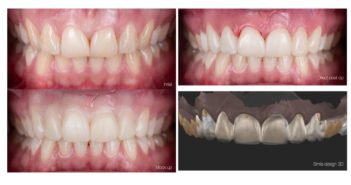

ET SI L A PHOTO DEVENAIT NOTRE MEILLEUR OUTIL CLINIQUE ?

INTRODUCTION : PHOTOGRAPHIER, UN ACTE CLINIQUE À PART ENTIÈRE La photographie a longtemps été perçue comme une activité annexe à…